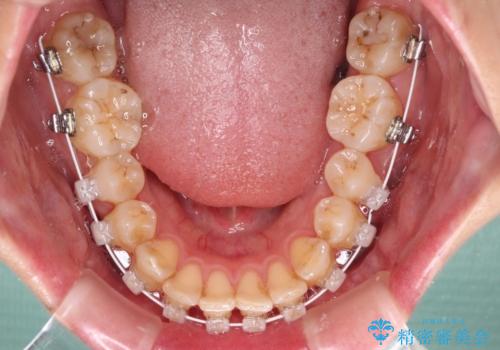

- 矯正装置

- 審美装置

- 前歯の突出感を気にして来院された患者様です。

左右ともに奥歯の咬み合わせが上顎前突となっており、上顎前歯が飛び出している状態でした。

奥歯の咬み合わせ改善が必要であるため、マウスピース矯正より確実に達成のできるワイヤー矯正にて治療を行うこととしました。